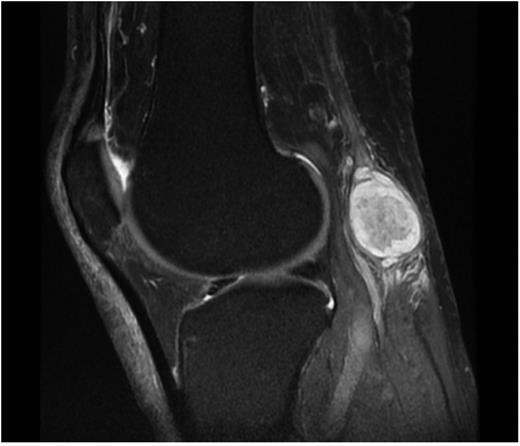

Fifty-eight-year-old man presented to the outpatient clinic of orthopaedics department with the complaints of slowly growing mass on his right popliteal region and mild pain and intermittent paresthesia of right leg and right foot. The patient emphasized that the mass existed for 2 years but has grown in the last 6 months. On physical examination, 4 × 2 cm mobile, solid mass was palpable at the posterior of the knee. There was no erythema, warmth or ulceration and Tinel's sign was positive. Sensory and motor examinations of lower extremity were normal. Ultrasound imaging showed that the mass was solid and separate from the adjacent muscles and tendons. MRI showed well-defined solid, heterogenous, dense mass originating from the tibial nerve (Fig. 1). Surgical exploration and excisional biopsy was performed. At prone position with longitudinal incision, popliteal region was explorated and tumoural mass originating from tibial nerve was dissected. Sheath of the nerve was incised longitudinally to minimize damage to the nerve fascicles and the mass was resected in en-bloc form by sharp dissection using the microscope with no complication. The patient was discharged at the post-op third day. At the third week of the operation, the patient was free of all complaints. Histopathological examination of the mass revealed hypocellular Antoni B and spindle-shaped Schwann cells containing Antoni A areas with nuclear palisading. Also immunohistochemical staining (S100+) confirmed the diagnosis of schwannoma.

Schwannoma is the most common benign neoplasm of the peripheral nerves and may originate from any of peripheral nerves. It is usually solitary, painless, encapsulated and well-defined, slowly growing mass [1–3]. In our case, tumoural mass was solitary and well-defined but painful. Tinel's sign can be important in differential diagnosis. Maraziotis et al. reported two cases of neurilemoma localized in the popliteal fossa. Both patients experienced non-specific symptoms, such as painful numbness and burning dysaesthesia, involving the lower extremity and Tinel’s sign was positive over the popliteal fossa in one of these cases [7]. In our case, Tinel's sign was positive. In the literature, tarsal tunnel syndrome secondary to tibial nerve schwannoma was reported and MR imaging was advised. Sometimes it is impossible to differentiate the schwannoma from neurofibroma or malignant peripheral nerve sheath tumours and biopsy can be a necessity to confirm the diagnosis. [3]. In our case, we also preferred to excise the tumour and confirmed the diagnosis by histopathological examination. Histopathological examination of the schwannoma reveals hypocellular Antoni B and spindle-shaped Schwann cells containing Antoni A areas with nuclear palisading. Also immunohistochemical staining (S100+) confirms the tumoural cells originating from schwann cells and the diagnosis of schwannoma [8]. In our case, necrosis, increased mytotic activity or atypical cells were not observed in histopathological examination and also positivity of S100 staining confirmed the diagnosis of schwannoma (Fig. 2 and 3). Surgical excision should be performed carefully not to damage the nerve fascicules [1]. After surgical excision, sometimes paresthesia may be seen but usually it resolves without any neurological problem and also recurrence of the tumour is very uncommon [1–3]. In this case, we did not meet any neurological complication. At the last control the patient was free of symptoms and there was no sign of residue or recurrence.